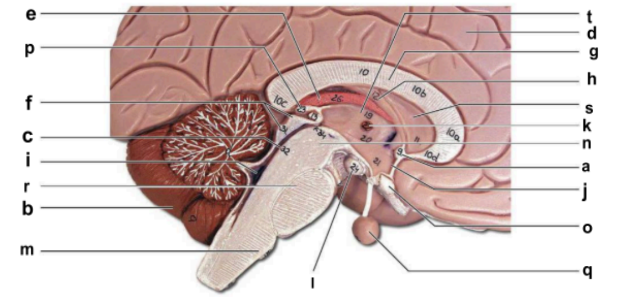

Identify the structure labeled “a” in the image.

anterior commissure

Identify the structure labeled “b” in the image.

cerebellum

Identify the structure labeled “c” in the image.

cerebral aqueduct

Identify the structure labeled “d” in the image.

cerebral hemisphere

Identify the structure labeled “e” in the image.

choroid plexus

Identify the structure labeled “f” in the image.

corpora quadrigemina

Identify the structure labeled “g” in the image.

corpos callosum

Identify the structure labeled “h” in the image.

fornix

Identify the structure labeled “i” in the image.

fourth ventricle

Identify the structure labeled “j” in the image.

hypothalamus

Identify the structure labeled “k” in the image.

interthalamic adhesion

Identify the structure labeled “l” in the image.

mammilary body

Identify the structure labeled “m” in the image.

medulla oblongata

Identify the structure labeled “n” in the image.

midbrain

Identify the structure labeled “o” in the image.

optic chiasma

Identify the structure labeled “p” in the image.

pineal gland

Identify the structure labeled “q” in the image.

pituitary gland

Identify the structure labeled “r” in the image.

pons

Identify the structure labeled “s” in the image.

septum pellucidum

Identify the structure labeled “t” in the image.

thalamus